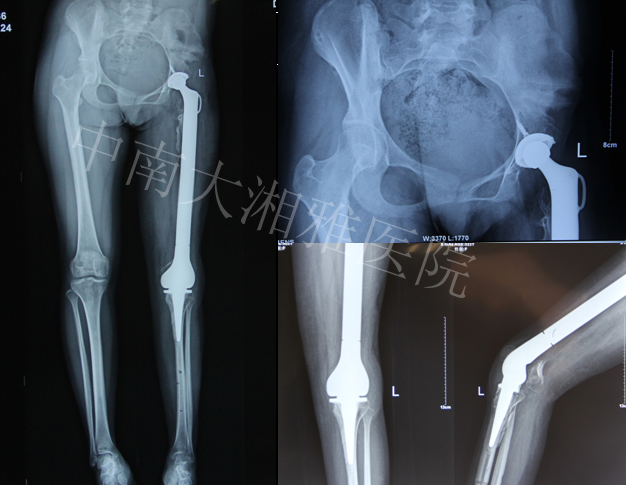

Final Game—2013年10月

术后2月复查—2013年12月